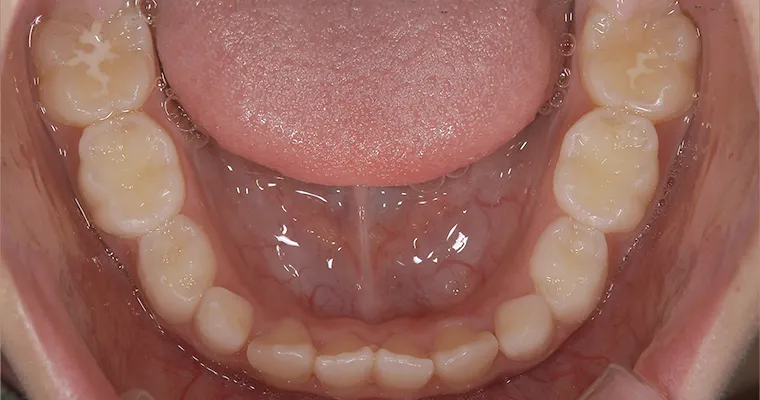

下顎咬合面観

BEFORE

AFTER

| 主訴 | 歯並びが悪い 乳歯と永久歯が重なっている 歯がまっすぐはえてこない |

|---|---|

| 治療期間 | 6-7ヶ月 |

| 治療費 | 440,000円(税込) ※調整、器具、治療後にお渡しするEFLine(矯正後の後戻りを防ぐ器具)も全て込みでの金額となっております。 |

| 治療内容 | 拡大床矯正 EF Lineで筋機能療法 |